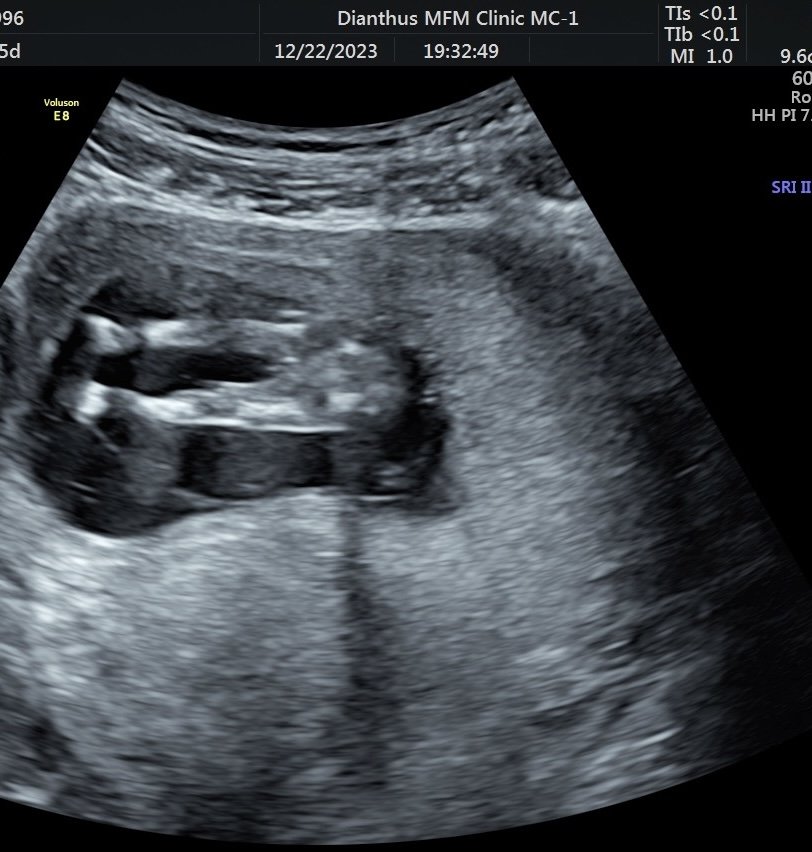

超音波是男寶還女寶

上週去照第一孕期高層次

腿腿中間時而凸時而不凸

好奇是弟弟還是妹妹> <